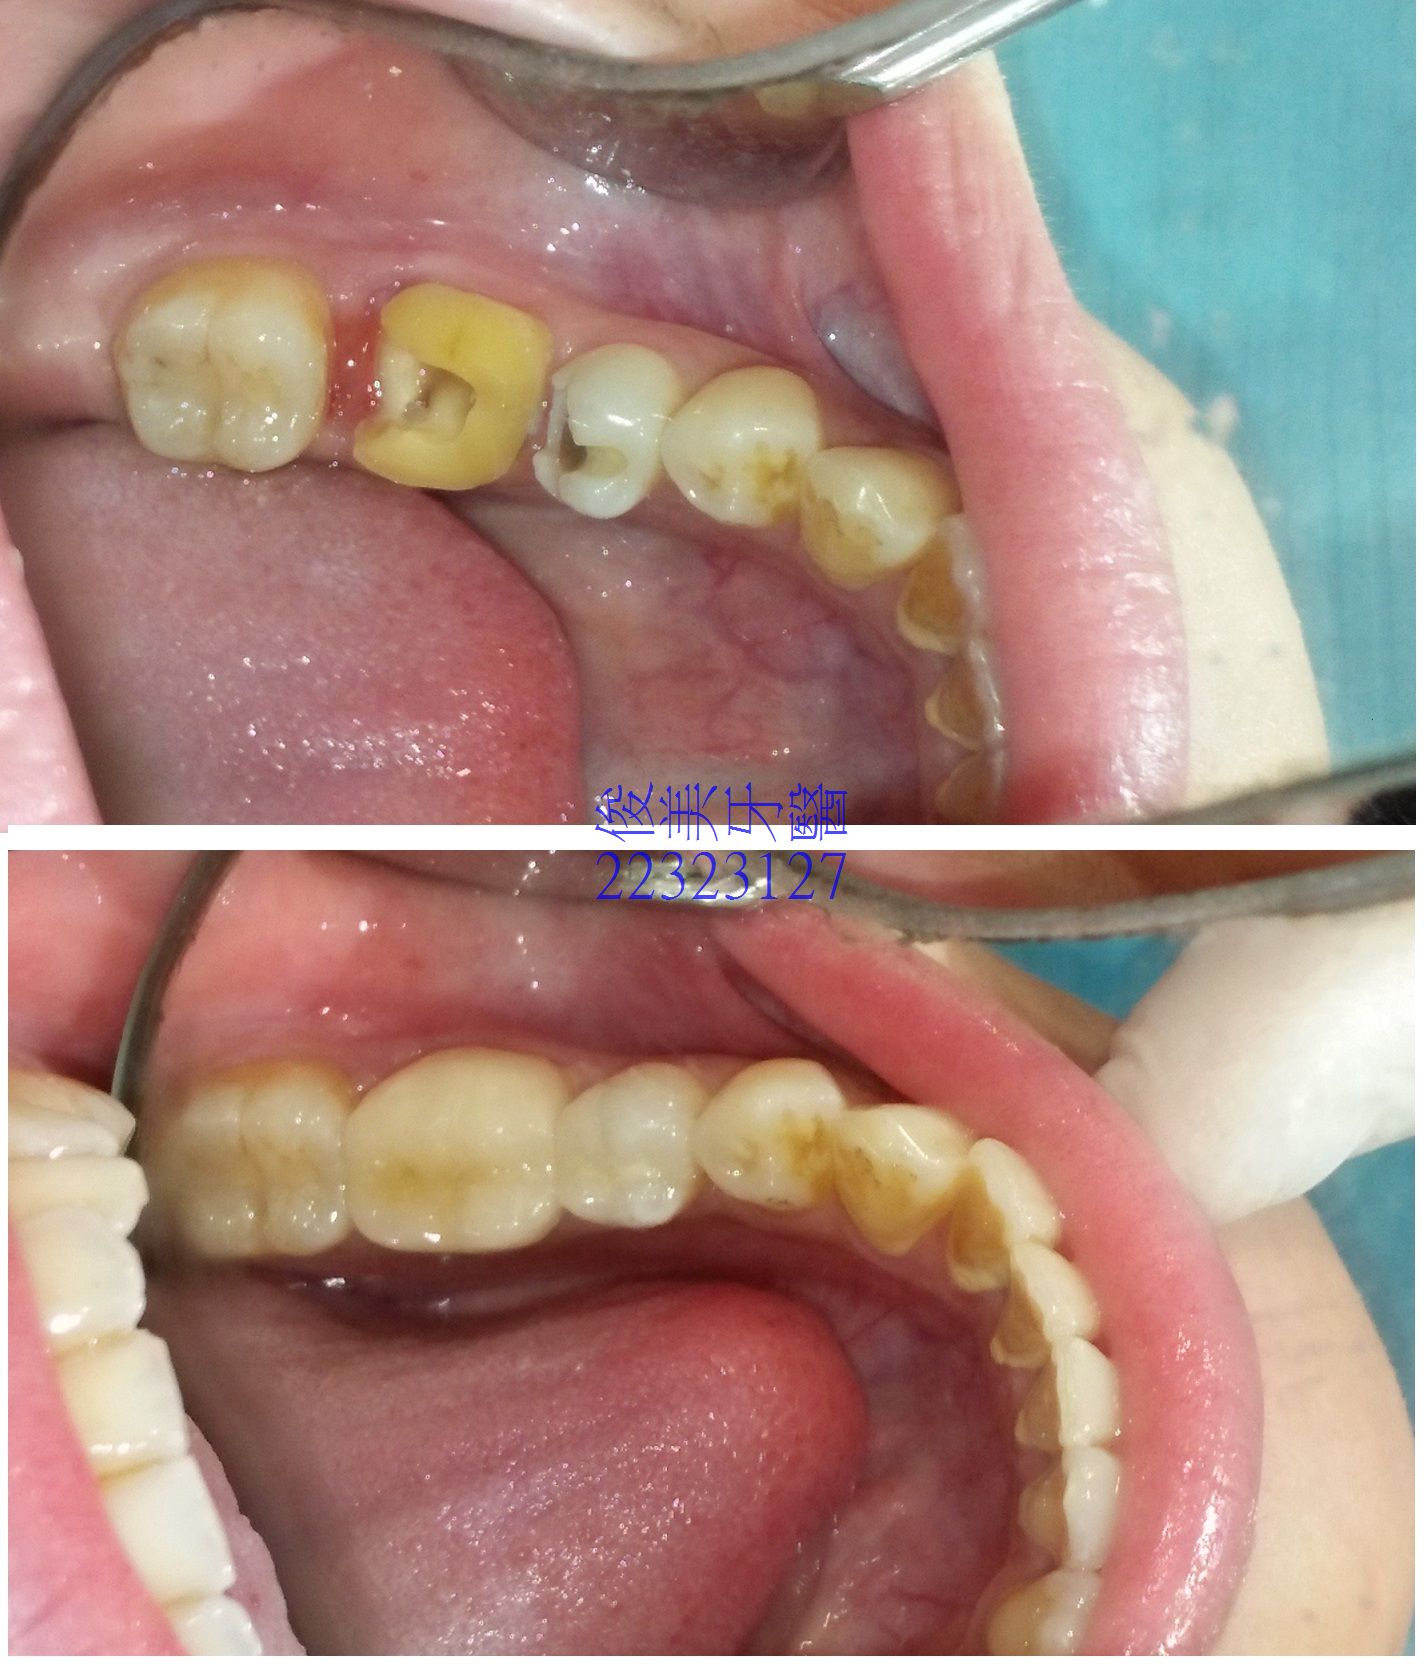

全瓷嵌體護套案例7

患者因未使用牙線,且大臼齒牙縫易塞,導致蛀牙蛀到神經,於治療後,聽從醫師建議做全瓷榫接式人工牙冠,因

臨界小臼齒也蛀牙,會敏感,因此一起修復,印模後,一週後回診裝牙。

患者裝 完牙後,直呼"太神奇了"!!

變身為完好的牙齒,一點都看不出來,牙縫也緊,可以用牙線清潔。

蛀牙深、敏感,在裝牙後,沒有症狀,無需抽神經。